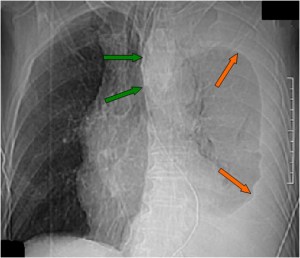

SIGNO DE LA SONDA NASOGÁSTRICA DESPLAZADA

El desplazamiento de la sonda nasogástrica a la derecha (que indica desplazamiento esofágico) en la radiografía de tórax, se ha descrito como el signo más fiable de rotura de la aorta torácica e indica la necesidad de realizar angioTC urgente. La primera imagen muestra el desplazamiento de la sonda (flechas verdes) así como un gran derrame pleural izquierdo (flechas naranjas).

En el corte de TC con contraste vemos la sonda desplazada a la derecha de la línea media (flecha azul), un hematoma mediastínico (flecha verde) provocado por la rotura aórtica (flecha naranja), y un hemotórax izquierdo (flecha amarilla).